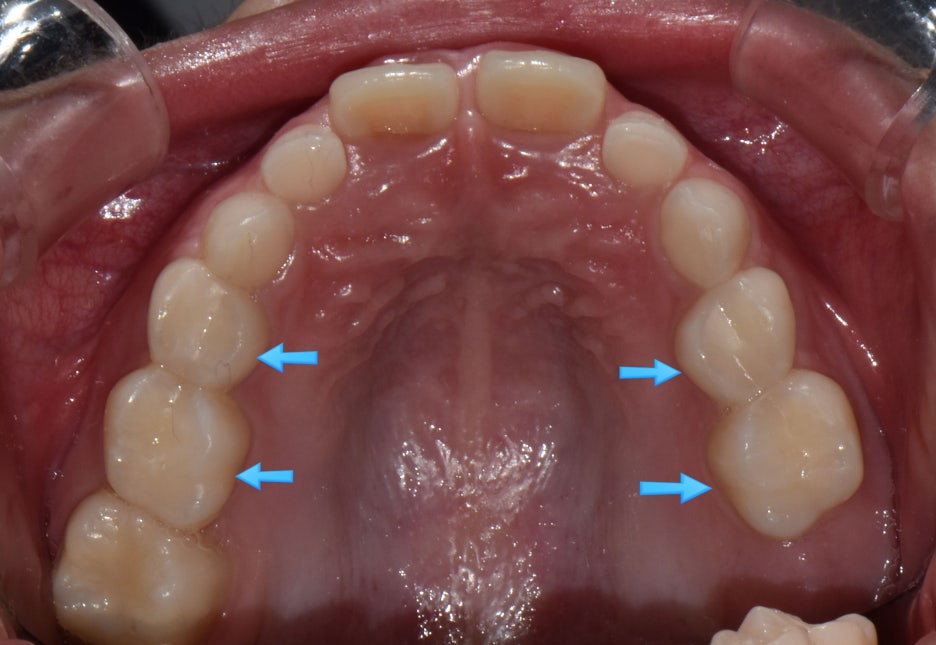

치아 사이충치를 레진으로 8개 치료, 아래 어금니 하나는 지르코니아 크라운으로 치료한 제 큰아이 입니다. (아이에게 동의를 구하고 올립니다.ㅎㅎ)